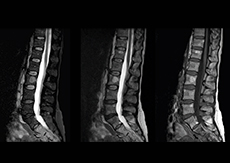

More information without extending time slot

“In our lumbar spine MRI, the value of mDIXON TSE is so obvious. Normally we perform T1 and T2 scans in sagittal and transverse orientation.It used to take too much time to add a sagittal T2 with good fat suppression.But now, using mDIXON TSE, we get the sagittal T2 fat suppressed images ‘for free’, that is: without adding time.”

“Diagnostically that is a great benefit. I sometimes see abnormalities in the fat suppressed sagittal T2 that would be quite challenging to notice in the T2 without fat suppression. There have been several diagnoses that I could make easier because of our exam setup with mDIXON TSE, such as sacrum insufficiency fractures and sacroileitis; these were more challenging with our previous exam setup.”